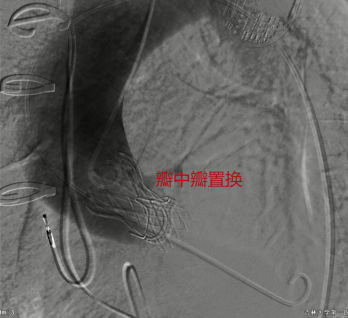

8月16日,吉大一院心脏外科TAVR手术团队为一名开胸瓣膜置换术后复发并伴有心力衰竭患者实施微创介入“瓣中瓣”手术,在此前置换的失功生物瓣膜内部成功植入新瓣膜,为患者再造“心门”。该手术为吉林省首例经导管主动脉瓣“瓣中瓣”置换术,填补了吉林省该领域治疗空白。

患者为59岁男性,曾于5年前开胸行主动脉瓣生物瓣膜置换术。半年前出现乏力症状,近两周乏力症状加重并伴有胸闷、胸痛、呼吸困难等,严重影响日常生活。患者辗转来到吉大一院心脏外科就诊,行心脏彩超等相关检查,发现此前植入的主动脉瓣生物瓣毁损,导致主动脉瓣再次出现中度狭窄兼关闭不全,继而诱发肺动脉压力增高、左房左室增大、右心功能减低,患者心功能EF值仅36%,出现心衰症状。经心脏外科专家会诊,患者主动脉瓣病变严重并伴有心衰,如果不尽快手术治疗,严重影响生活质量并随时有猝死风险。患者身形消瘦,体重不足60公斤,心脏周围组织严重粘连,再次实行外科开胸手术存在操作复杂、手术时间长、创伤大、出血多等问题。遂决定采取经导管主动脉瓣“瓣中瓣”置换术,此术式可不拆除原有的人工生物瓣,无需心脏停跳手术,免除再次开胸。

8月9日,心脏外科主任马大实统筹,教授高永生主刀,医生杨立明、刘宇帅辅助,在麻醉科、第二手术室、超声诊断中心—心脏超声科等科室的密切配合下,为患者实施经导管主动脉瓣“瓣中瓣”置换术。患者术后主动脉瓣贴合良好,无返流、无瓣周漏,憋闷胸痛症状明显改善,心功能逐渐恢复正常,术后第4日顺利康复出院。